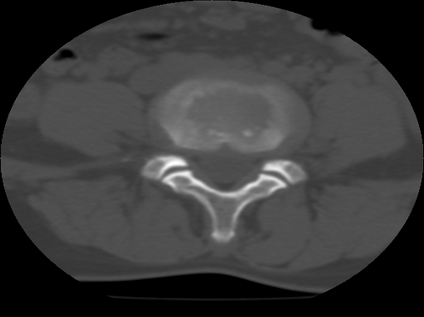

标题: CT21469:腰椎局限性呈高密度,什么原因? [打印本页]

标题: CT21469:腰椎局限性呈高密度,什么原因?

34y,做腰椎间盘扫描发现的,战友们讨论一下原因!

腰椎前缘密度较均匀增高,边缘清晰;考虑腰椎致密性骨炎可能。

考虑骨岛。患者增生硬化不明显,男34岁,腰椎非致密性骨炎好发部位、性别。

支持致密性骨炎,腰椎前缘也是致密性骨炎好发位置.

考虑腰椎致密性骨炎,其实腰椎前上角是也是致密性同炎的好发部位,只是没能引起同志们的注意。

dxy此病例程教授会诊过了,考虑骨岛。